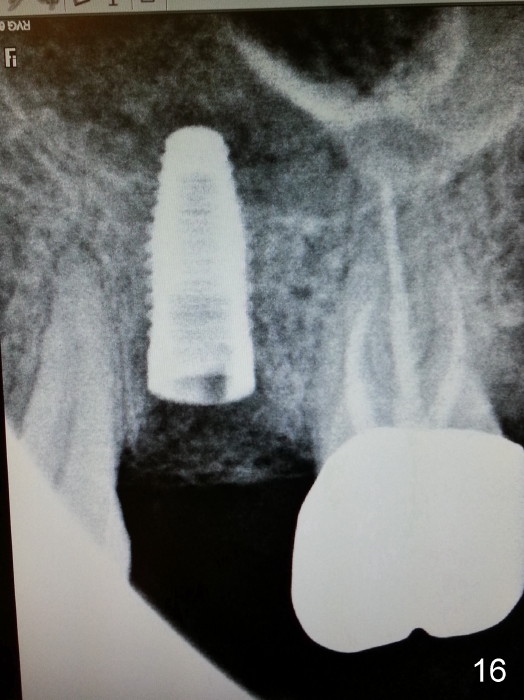

Grafting Following Immediate Implant (Photos Provided by Xue Steven, DDS)

The tooth #13 appears to be affected by periodontits and occlusal trauma (Fig.1*). After using a periotome (Fig.2), the tooth is extracted (Fig.3). The buccal flap is raised (Fig.4). Gingival graft is to be harvested from the site of #15 (Fig.5). The tissue is elevated buccally (Fig.6) and separated (Fig.7). The donor site is covered by a collagen membrane (Fig.8*). A diamond bur is used to induce bleeding from the socket (Fig.9*). Osteotomy is initiated (Fig.10) and enlarged (Fig.11,12). A tapered implant is being placed (Fig.13-15) following internal sinus lift (Fig.16,17). The implant is placed subcrestally, followed by bone graft (Fig.18), soft tissue graft (Fig.19), and suturing (Fig.20 <, Fig.21).